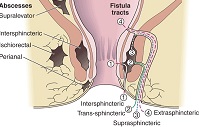

Types

There are basically 2 broad groups of anal Fistula in clinical practice - simple and complex anal Fistula.

The 'complexity' of the anal Fistula is basically dependent on:

- The amount of anal sphincter muscle involvement

- Presence of more than one anal Fistula (secondary tract and/or with abscess cavity)

- Anal Fistula with tracts above the anal sphincter complex or with the internal opening in the lower rectum or with the external opening further away from the anal verge

- Anal Fistula associated with other diseases (eg. Crohn's disease, tuberculosis)

'Complex' anal Fistula is a more severe form of anal Fistula. They will definitely require more complicated treatment. Sometimes, the treatment for these Fistula is carried out in stages.